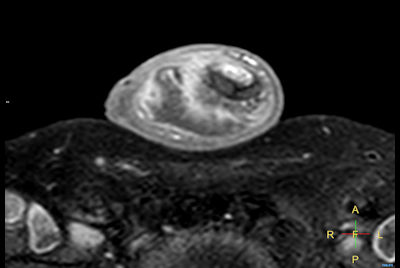

Finger with giant cell tumor

Imaging with the dS 16ch Small Extremity coil

Hand/Wrist with tumor